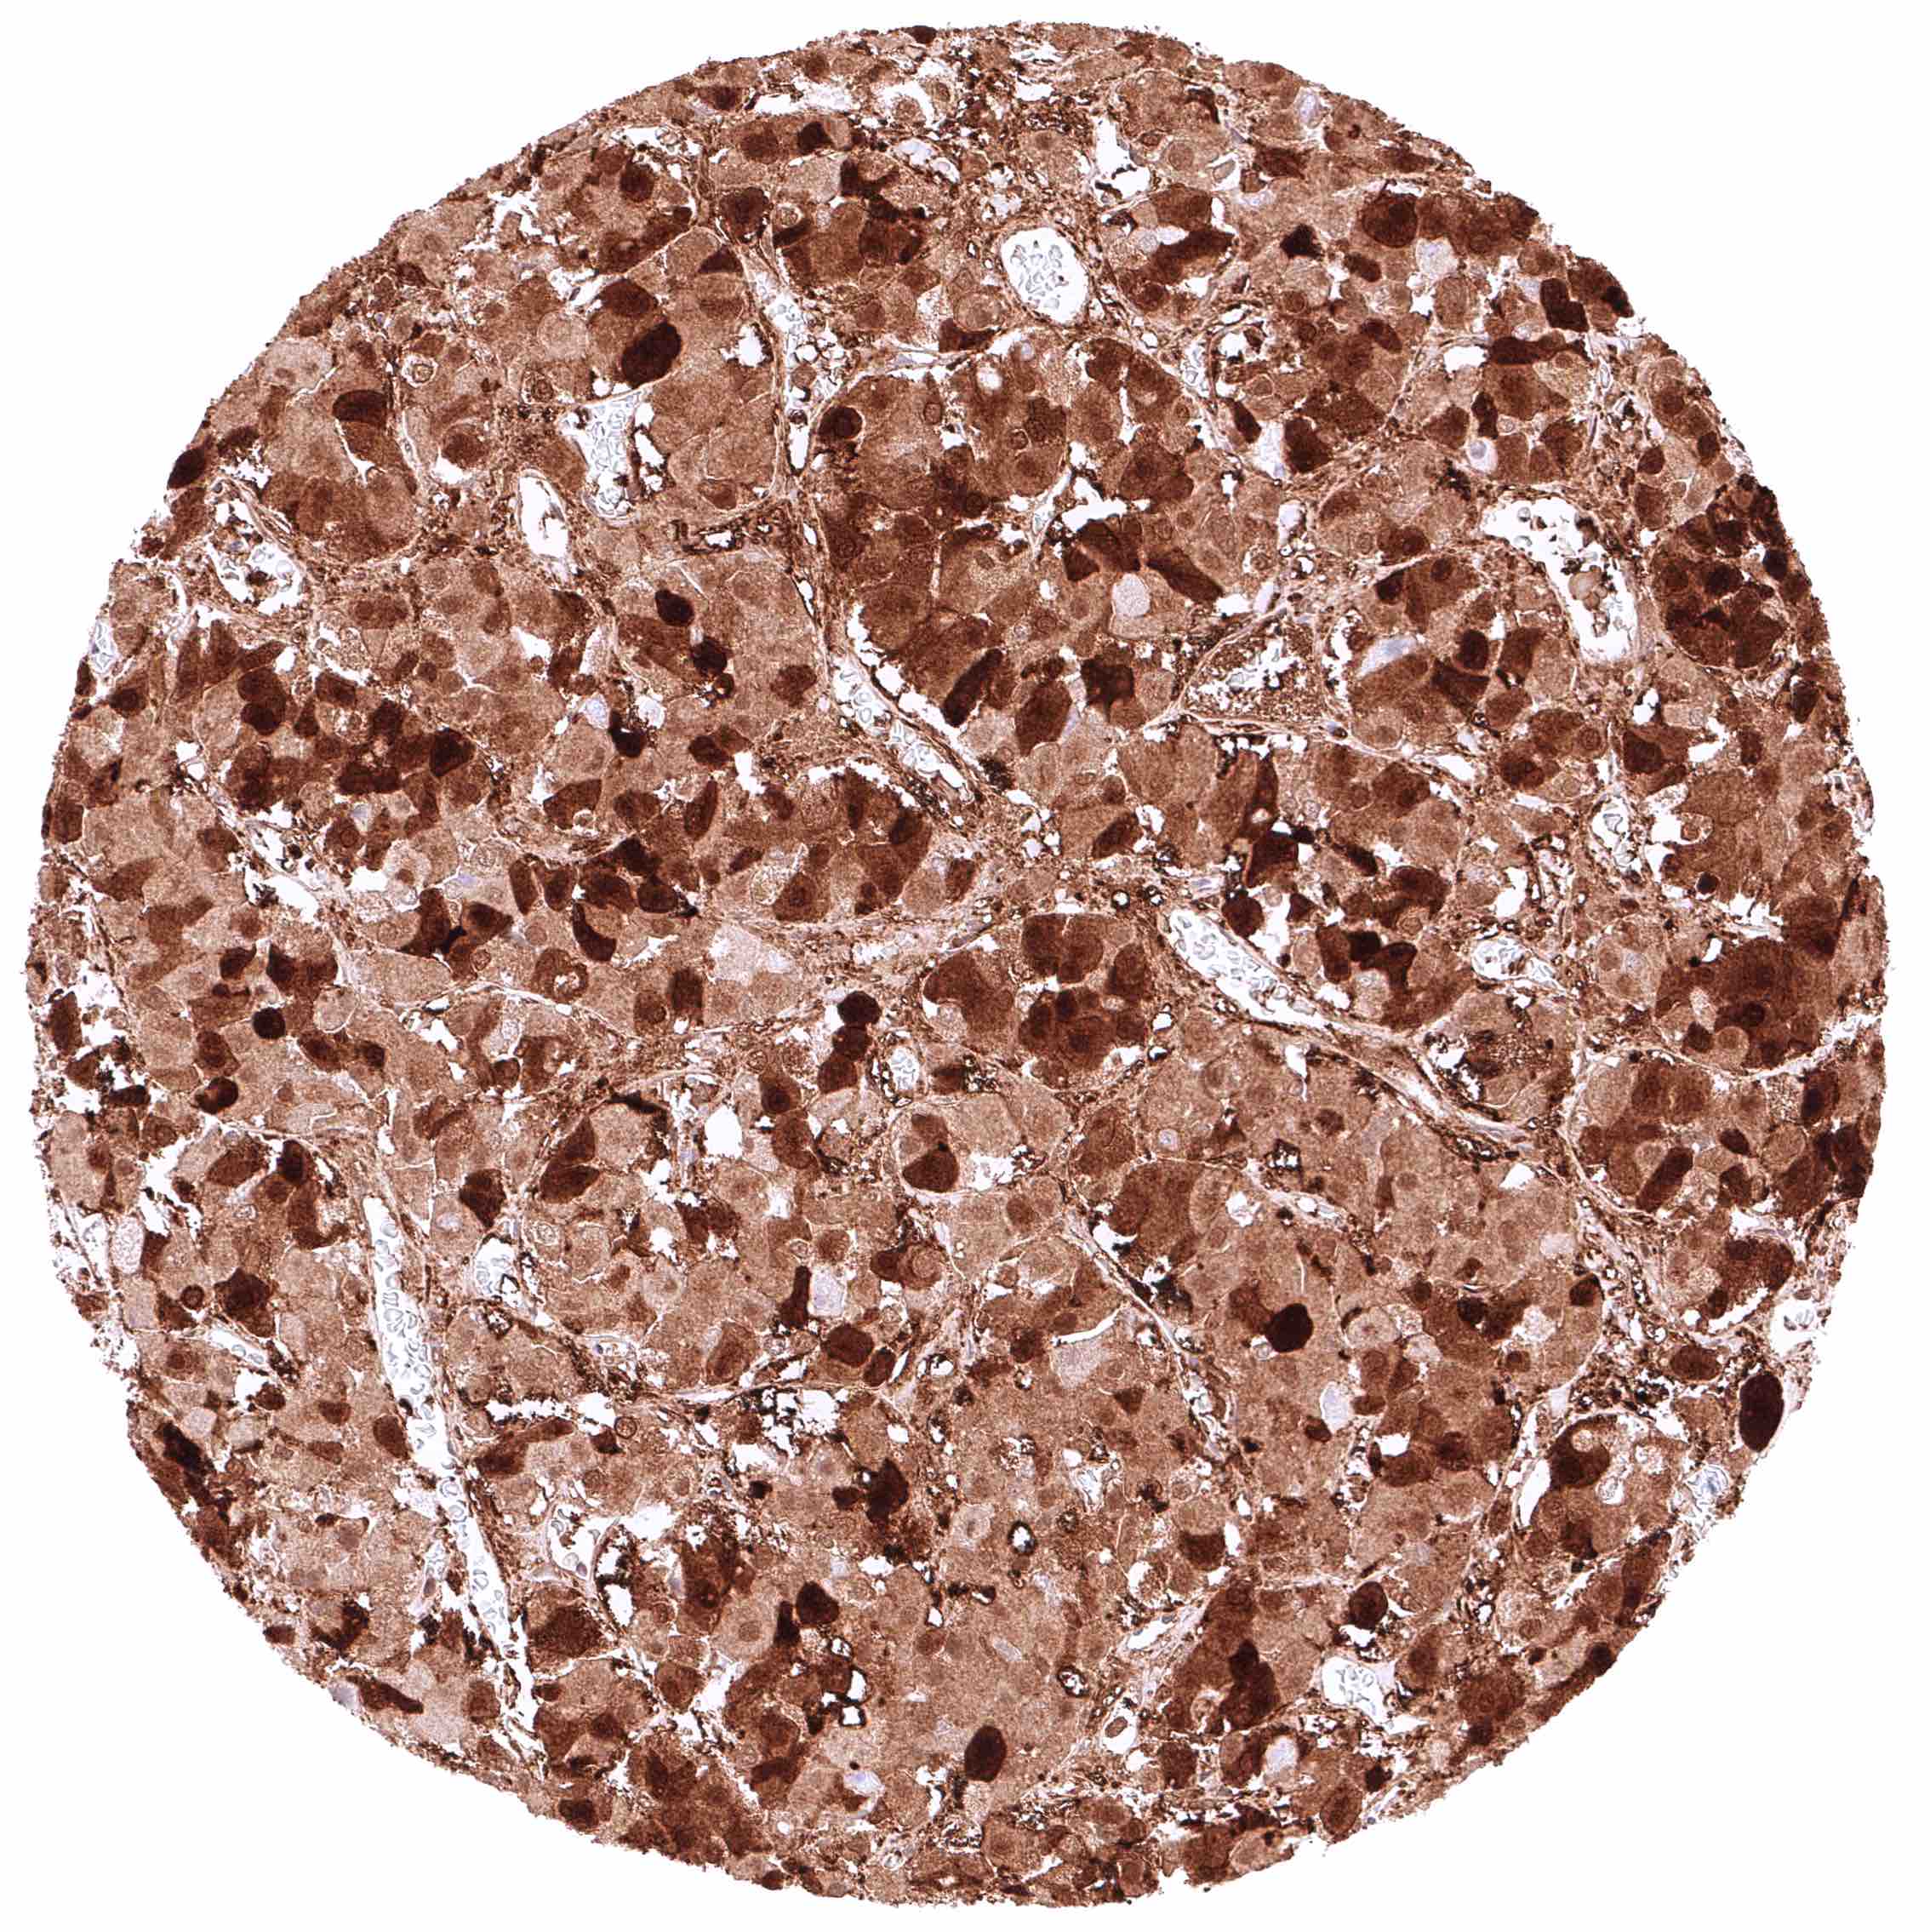

Liver – Weak to moderate, cytoplasmic GSTP1 positivity of sinus endothelial cells while staining is stronger in Kupffer cells. Hepatocytes are GSTP1 negative.